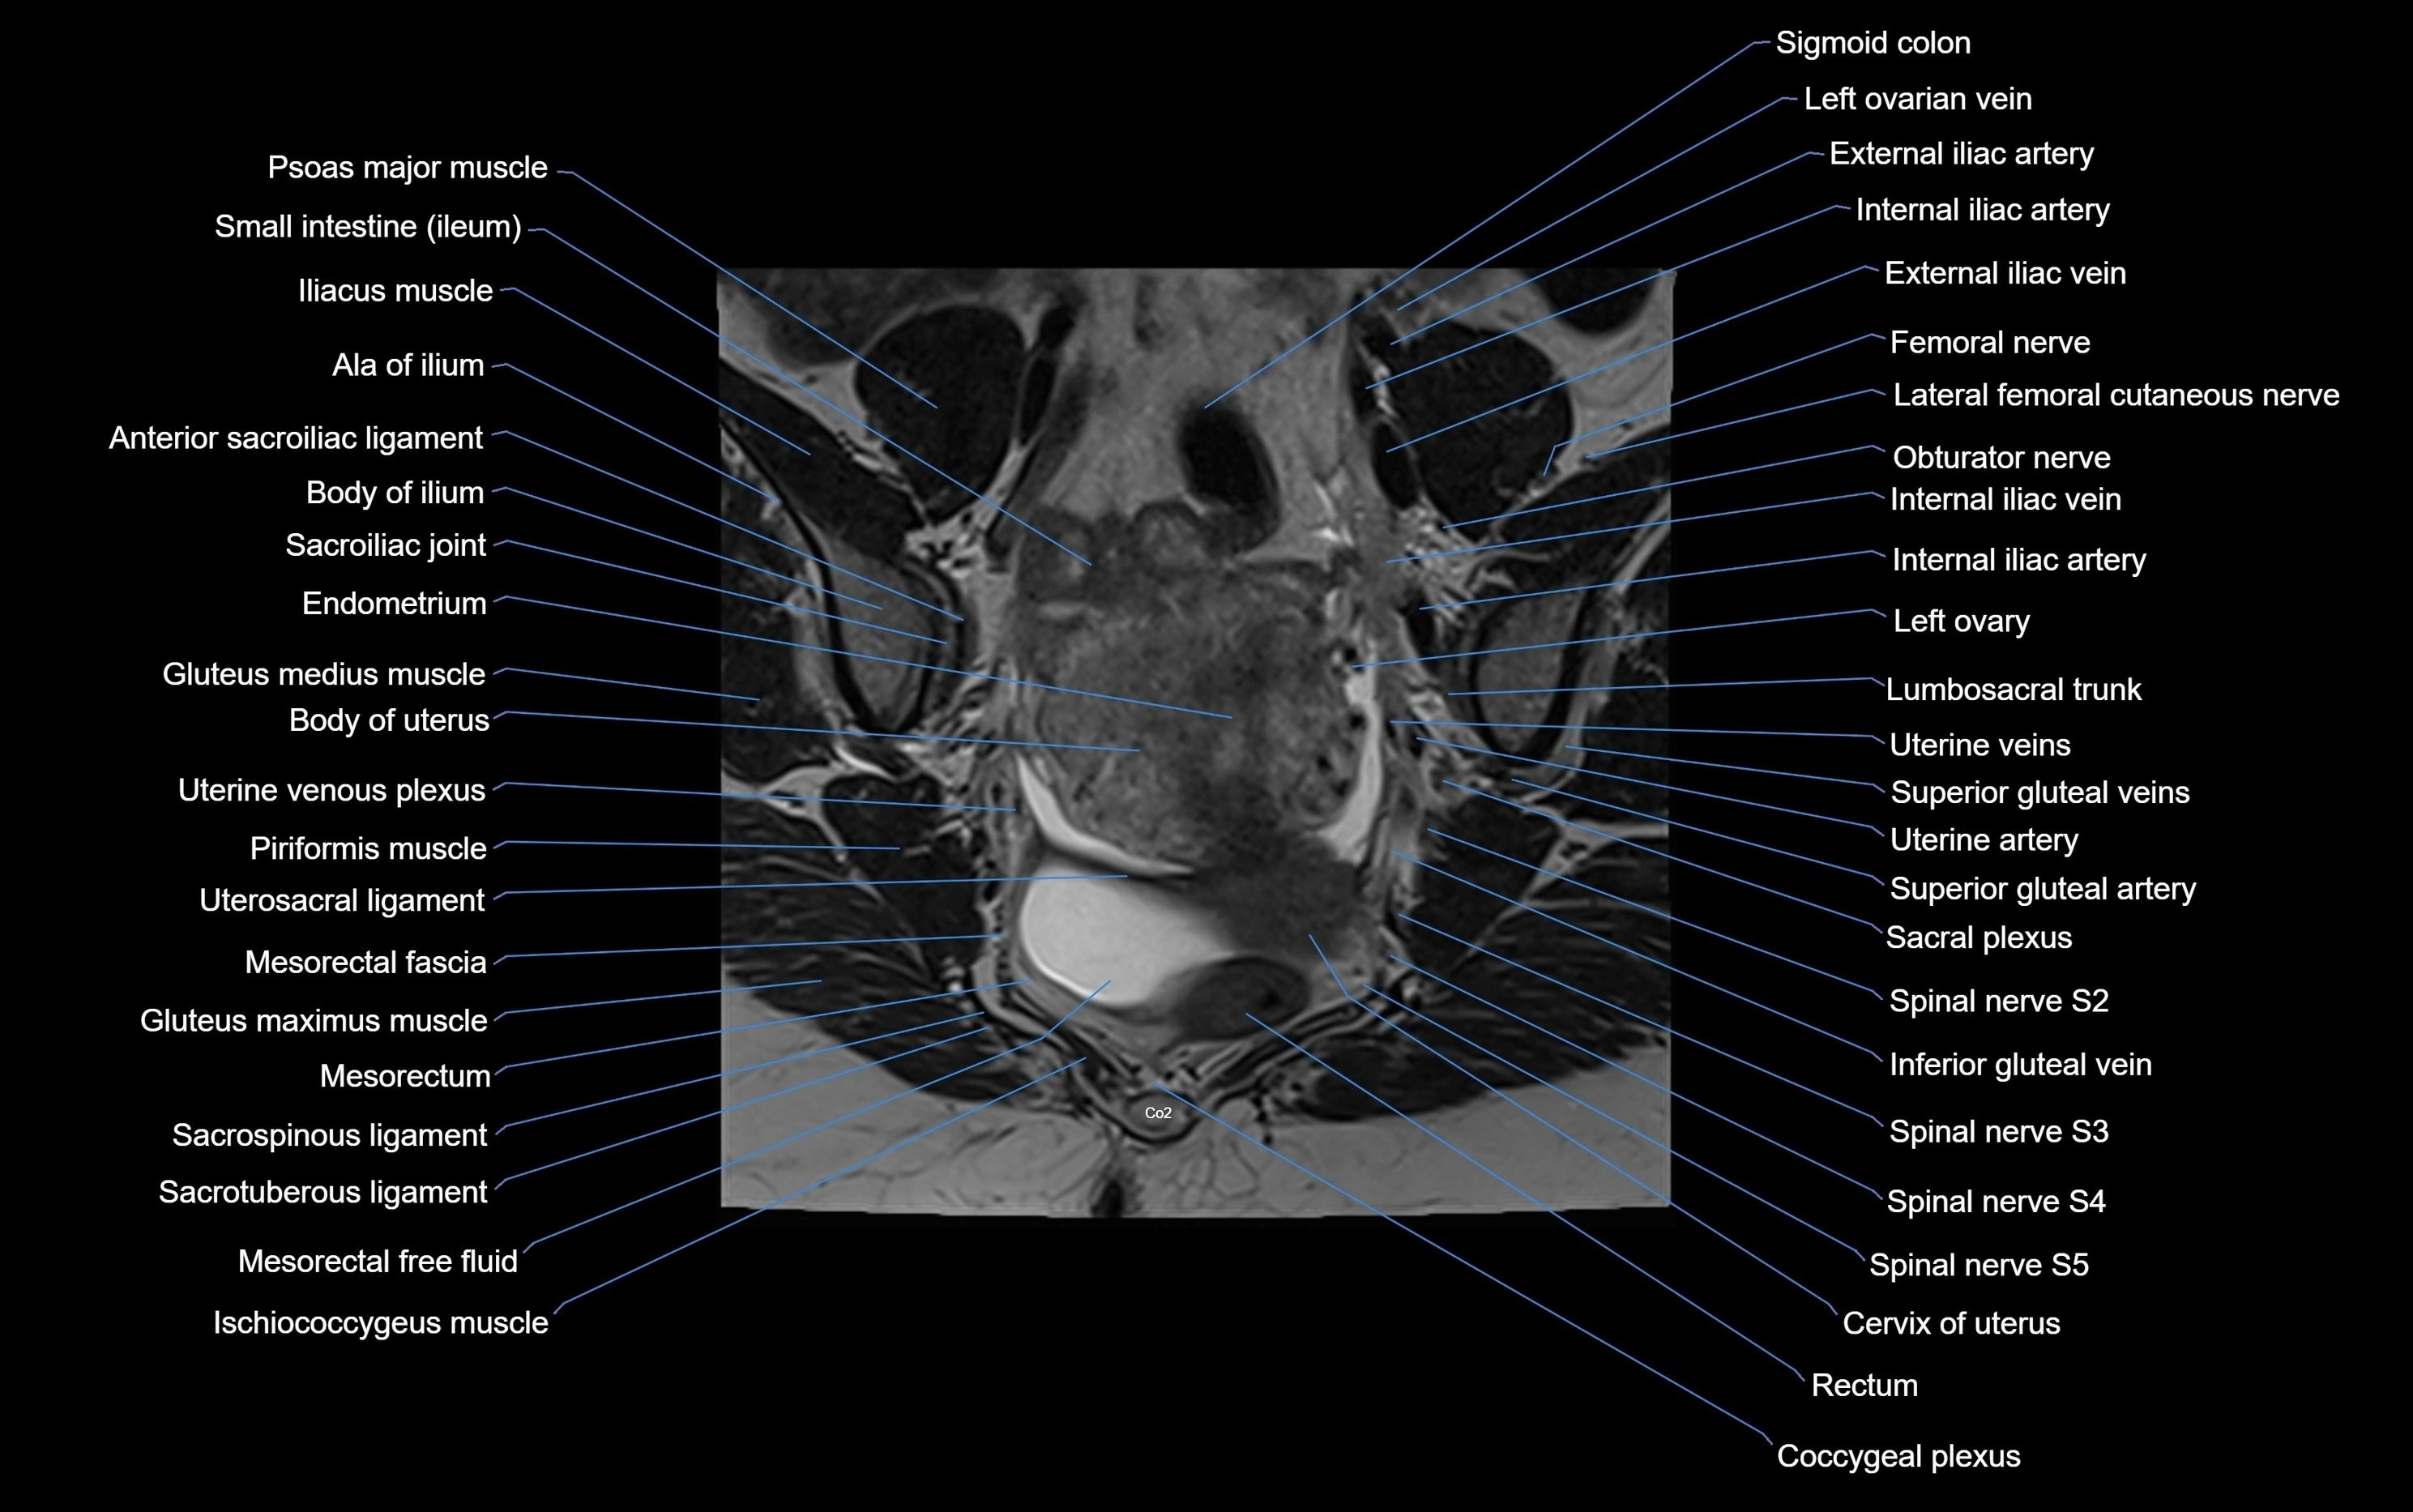

MRI Appearance

T1-weighted images:

• Cortical bone appears very low signal (dark); marrow shows intermediate signal

• Iliac fossa fat is bright against low-signal cortex

T2-weighted images:

• Cortical bone remains dark

• Marrow signal varies depending on fat content; edema or tumor shows hyperintensity

STIR:

• Suppresses fat, making bone marrow edema, fractures, or infiltrative lesions appear bright

• Excellent for trauma, sacroiliitis, and metastatic evaluation

T1 Fat-Saturated (Pre-contrast):

• Marrow: intermediate signal, fat suppressed

• Useful for detecting subtle marrow abnormalities adjacent to iliac cortex

T1 Fat-Saturated Post-Contrast (Gadolinium):

• Enhances vascularized structures, marrow pathology, tumors, and inflammatory changes

• Highlights soft tissue or bone invasion in pelvic neoplasms

MRI Non-Contrast 3D Imaging:

• Provides 3D morphology of iliac wing, crest, and articulations

• Used in preoperative planning for pelvic surgery and trauma reconstruction

MRI image

image